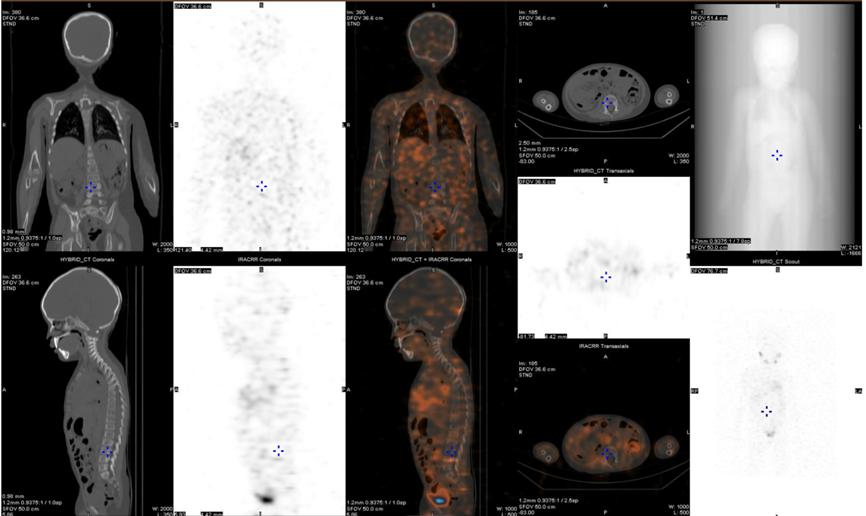

PET/CT(2021.08.14)

中上腹腔见多发不规则巨大囊实性占位(最大层面约14.7cm × 12.2cm × 13.7cm),实性区代谢增高,考虑恶性肿瘤,以NB可能大。左侧膈上、肌脚后间隙、右肾门区及腹膜多发高代谢肿大淋巴结及软组织包块,考虑转移。

2022.09.12(第2周期后)

复查PET/CT:未见明确高代谢灶。